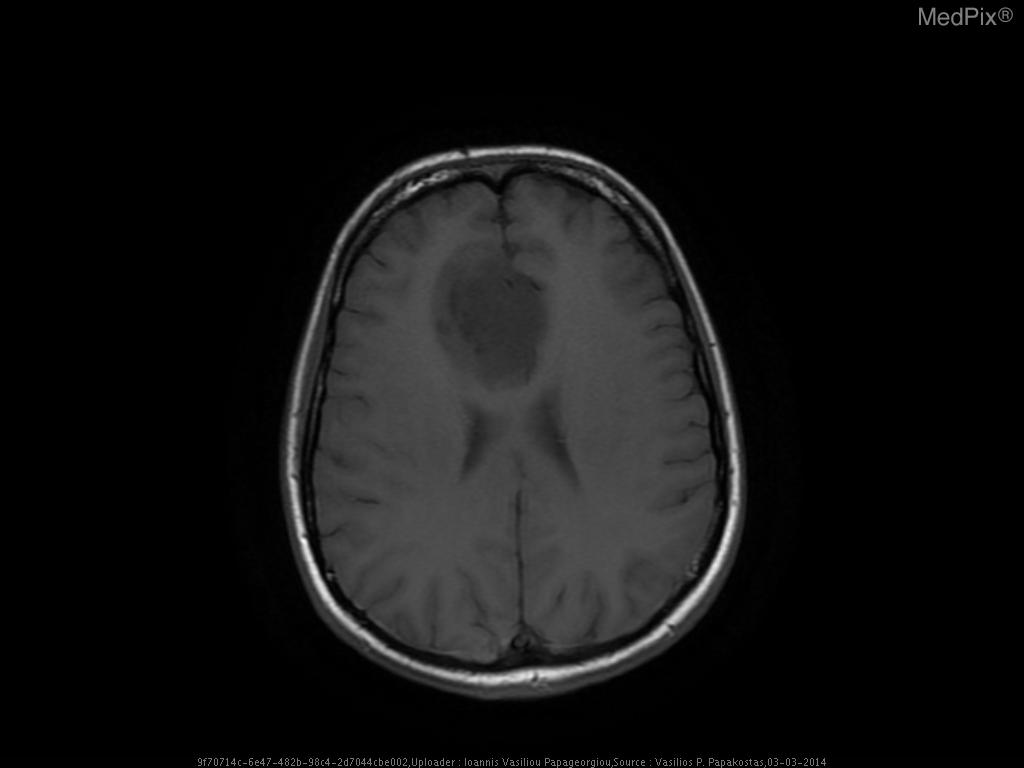

- Axial T1-weighted MRI brain shows a poorly defined, expansile lesion involving the image-right (patient-left) frontal lobe.

- The lesion demonstrates low T1 signal intensity relative to normal cortical gray matter.

- Minimal or no associated enhancement or hemorrhage visible on this non-contrast sequence.

- Mild mass effect evidenced by effacement of adjacent cortical sulci and mild displacement of the local midline toward image-left (patient-right).

- Gray-white differentiation appears blunted within the lesion region, suggesting infiltrative rather than circumscribed growth.

- No overt necrosis, cystic change, or intralesional hemorrhage visible on this slice.

- Surrounding brain parenchyma shows mild T1 hypointensity, potentially reflecting mild edema or infiltration.

- Ventricles appear slightly compressed on the image-right (patient-left) side, consistent with localized expansile mass effect.

Low-grade diffuse astrocytoma (WHO Grade

2). This is favored because of the nonenhancing, poorly marginated, T1-hypointense and mildly expansile frontal lobe lesion without necrosis or hemorrhage—classic for a diffusely infiltrative glioma of low grade. Lack of enhancement or necrosis argues against high-grade glioma. Context consistency:

Consistent — the provided context aligns well with the imaging findings of a low-grade diffuse astrocytoma. Confidence: 90%.